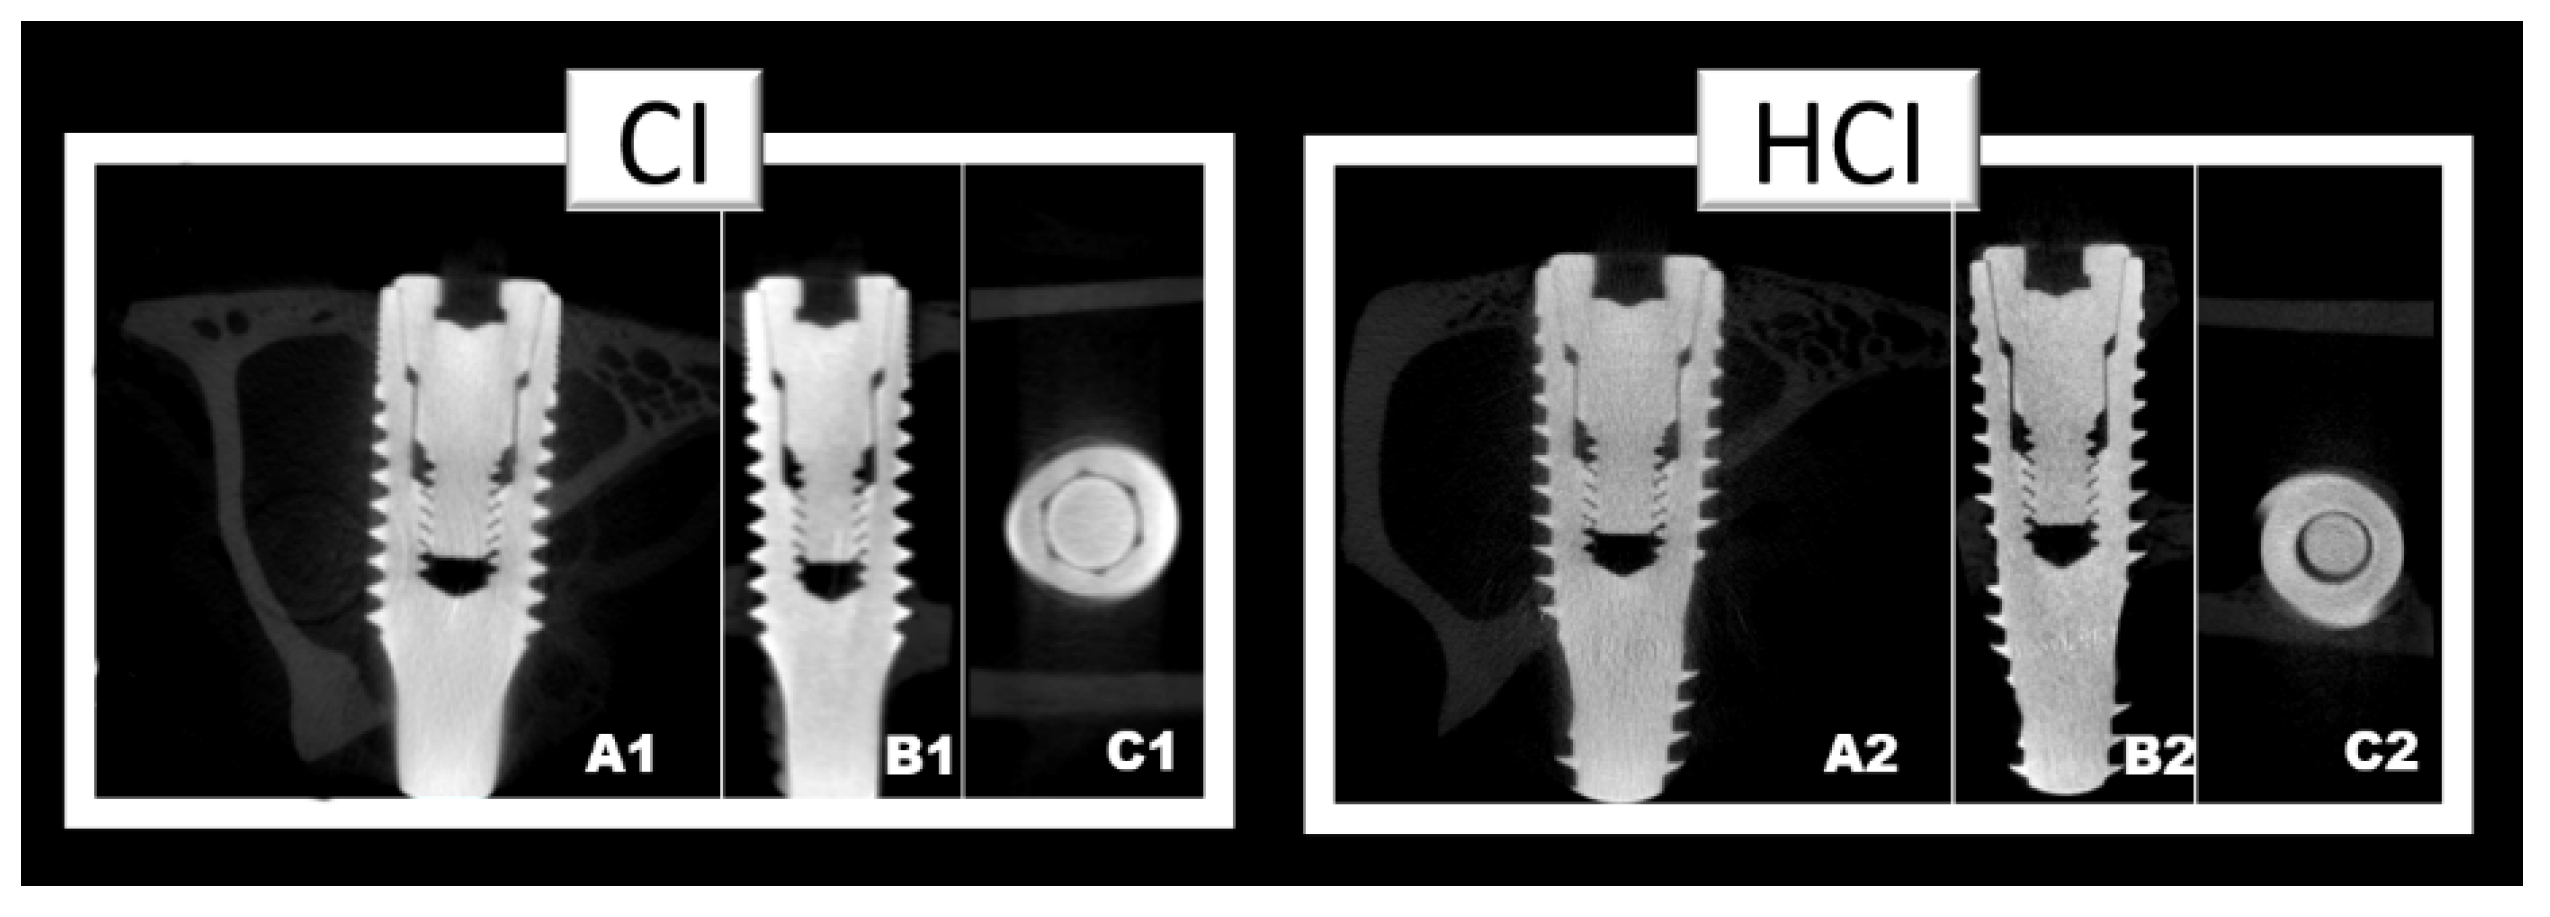

There were no differences between groups regarding the BV/TV data. However, there was a progressive increase in this parameter with the increase in the time of the experimental periods in both groups. Figure 5 and Table 2 show the data on the mean and standard deviation from the BV/TV data obtained through microtomographic analysis of all groups. Figure 6 shows the microtomographic images of the implants with the different macrostructures.

Figure 6.

Microtomographic images representative of implants with different macrostructures CI: Cylindrical Implant (1) and HCI: hybrid conical implant (2). Axial slice (A); Sagittal slice (B); and Coronal slice (C).